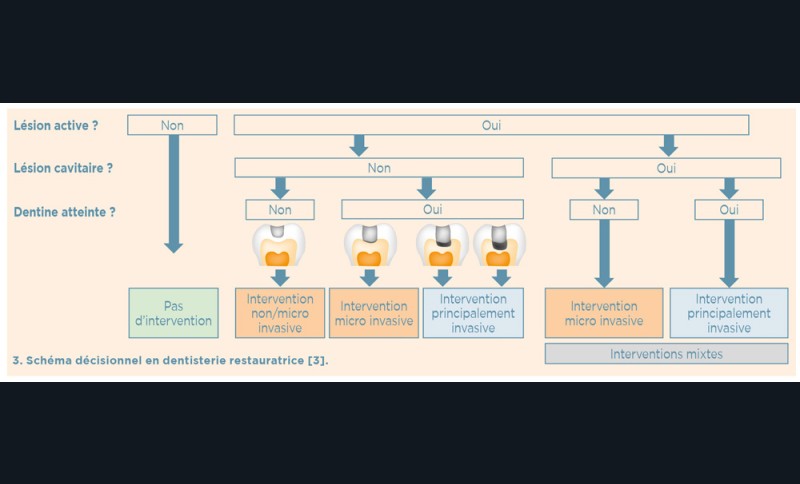

Le choix de la prise en charge de la lésion carieuse dépend de trois critères fondamentaux : l’activité de la lésion carieuse (active ou arrêtée), la présence ou non de cavitation et l’accessibilité (site proximal difficile d’accès) (fig. 3).

La prise en charge de la lésion carieuse se fait :

- soit de façon non invasive : motivation du patient à l’hygiène interdentaire et utilisation de techniques non invasives de reminéralisation ;

- soit de façon micro invasive en utilisant les techniques d’érosion/infiltration ;

- soit de façon invasive a minima. Cette économie tissulaire peut se faire notamment avec l’utilisation de fraises adaptées et minimalement invasives (fig. 4).